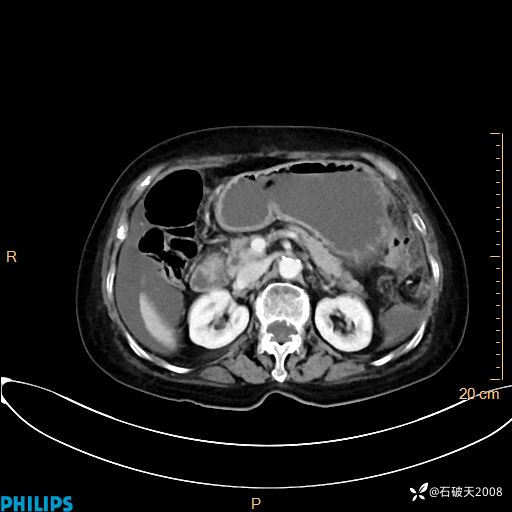

MIP